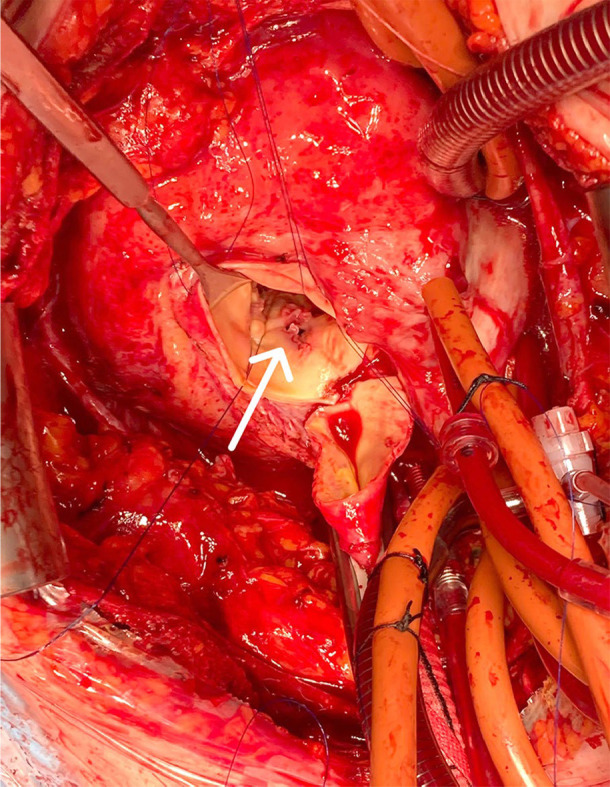

Surgical approach to complicated transcatheter aortic valve implantation endocarditis.